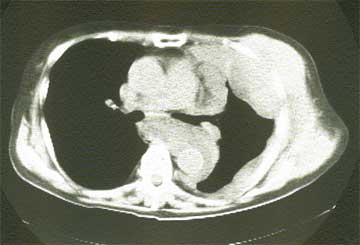

悪性胸膜中皮腫は肺の外側を薄く包む胸膜に、悪性腹膜中皮種は腹部の外側を包む腹膜にそれぞれできた悪性腫瘍です。最初の症状は、悪性胸膜中皮腫では息切れや胸痛が多く、悪性腹膜中皮腫では腹部膨満感や腹痛等で気づく事が多いとされます。

悪性中皮腫の診断は、レントゲン写真やCTや超音波写真の後に行われる、胸水や腹水の穿刺のよる細胞診断、その後の胸腔鏡や腹腔鏡等による組織診断に基づいて行われます。

(写真 悪性胸膜中皮腫CT像)

複数の免疫染色により、肺癌やその他の癌の転移との区別がつけやすくなってきました。但し胸水や腹水の出現時に悪性所見を呈さない例もあり、診断まで数ヶ月以上かかる事がやむをえない場合もある、診断の難しい疾患である事は今も変わりはありません。2018年の中皮腫について詳しく知りたい方は、当HP内の「中皮腫」をご覧ください。この病気について詳しくお知りになりたい方は、ひまわり診療所HP をご覧ください。